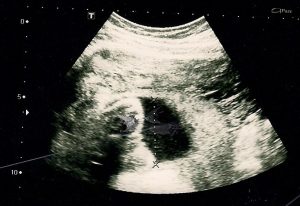

O que vai avaliar o excesso ou a falta de líquido na gravidez é o exame de ultrassom. É claro que isso vem acompanhado de alguns sinais, como a pele muito esticada e um crescimento muito repentino do útero. O médico também vai avaliar o tamanho do útero em comparação com a fase da gestação e pode levantar suspeitas sobre o excesso ou a falta de líquido amniótico.